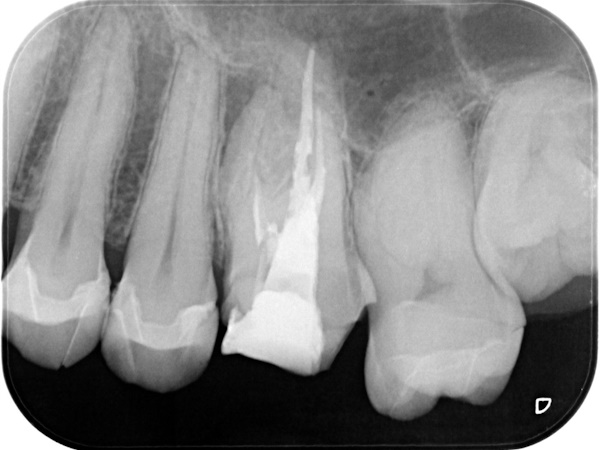

初診時